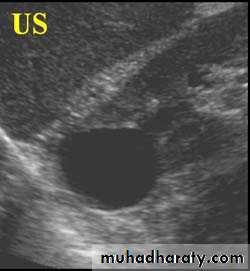

US :-

shows echo-free cystic lesion with posterior enhancement.